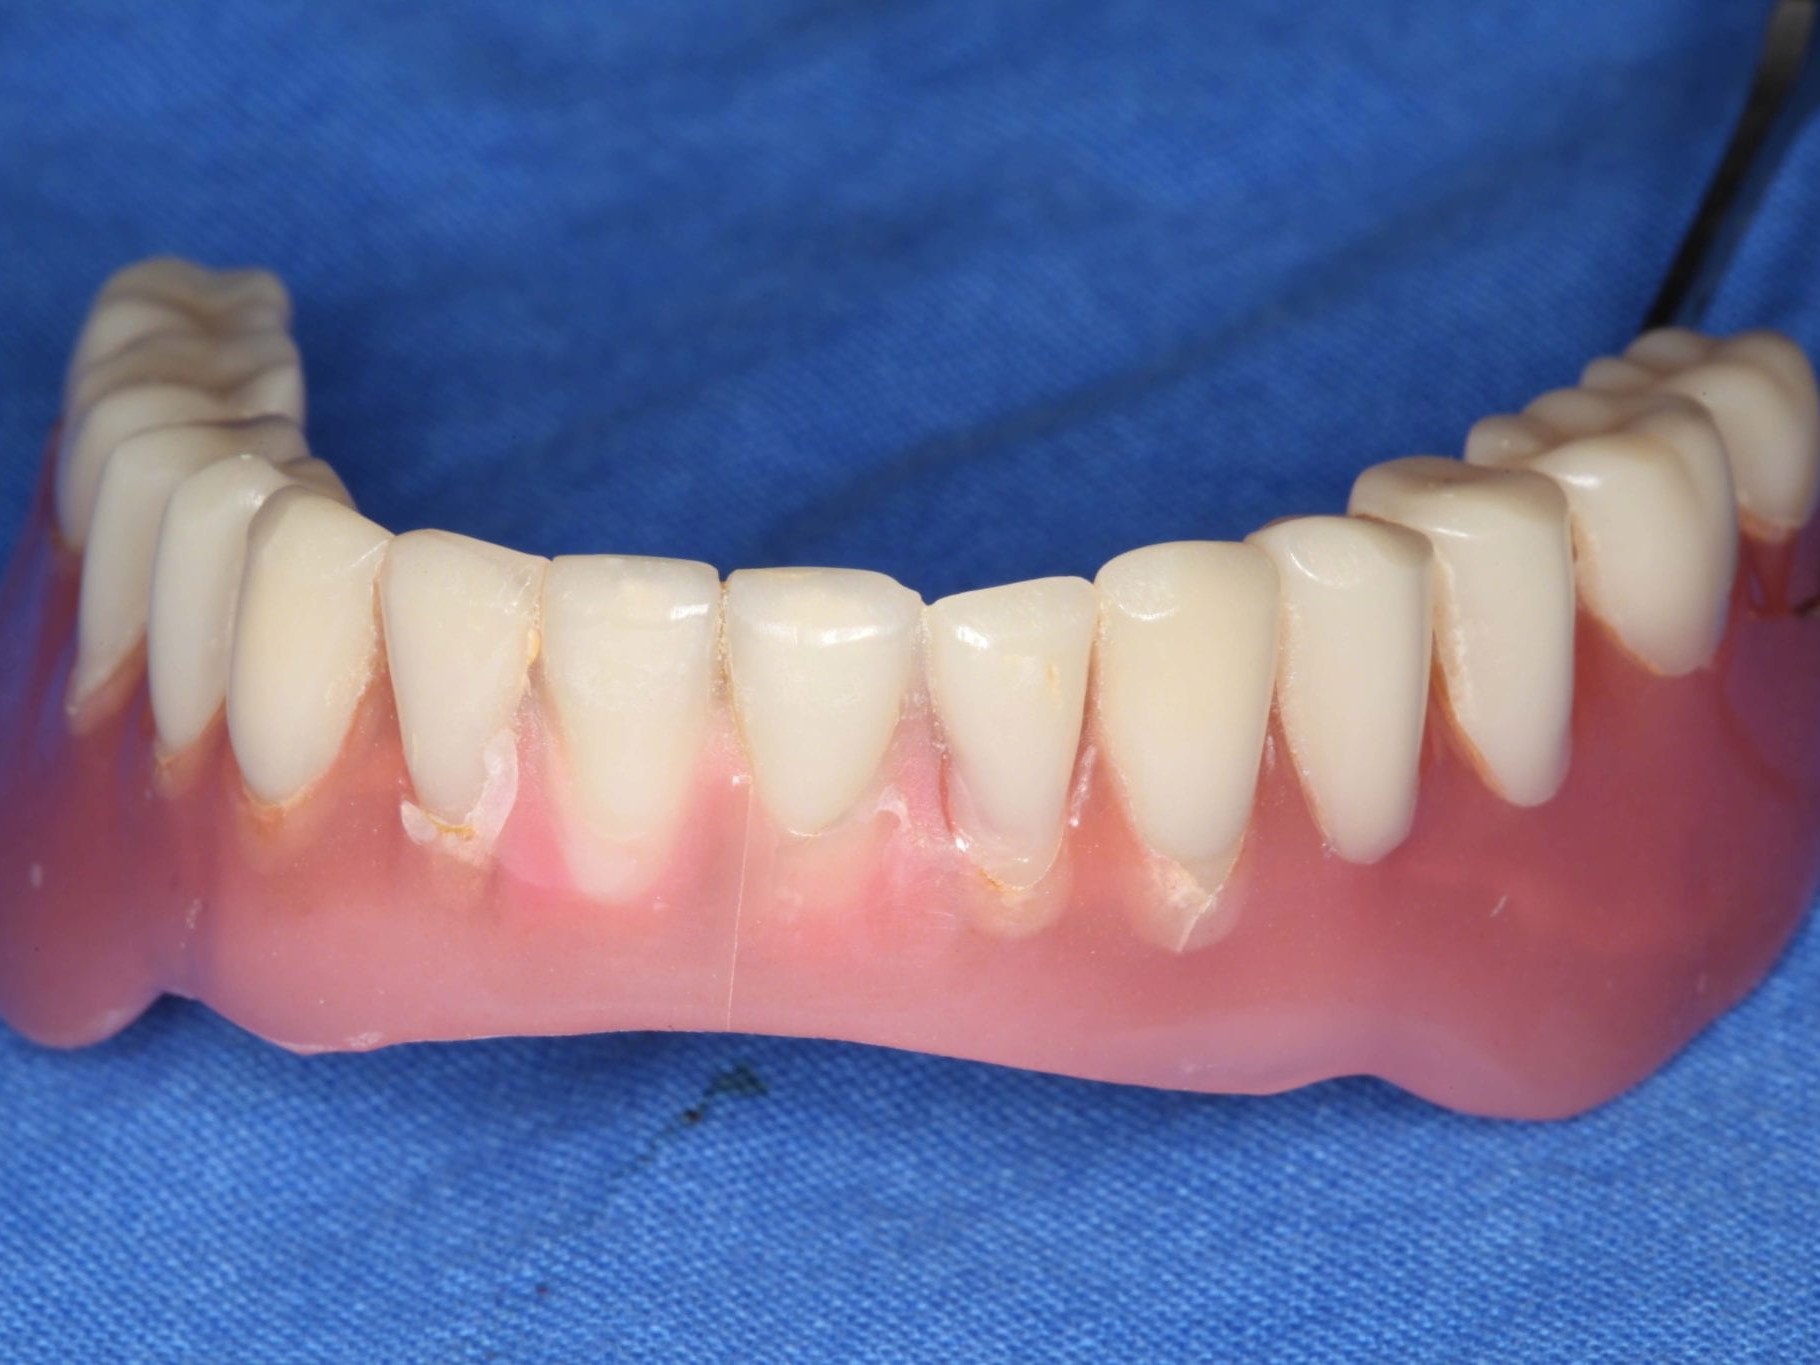

Das Beispiel zeigt eine 76-jährige Patientin, die seit Jahren einen herausnehmbaren Zahnersatz akzeptieren musste (Abb. 1-4), obwohl ihr Wunsch nach festsitzendem und damit jugendlich anmutendem Zahnersatz bestand. Oft wird der Seniorengruppe herausnehmbaren Zahnersatz mit dem Argument besserer Reinigungsfähigkeit empfohlen, obwohl Interesse und Akzeptanz an zahnärztlicher Vorsorge und Prophylaxe gestiegen sind. Laut DMS VI gehen 72,2% der Senioren regelmäßig zur zahnärztlichen Kontrolluntersuchung. Der Patientenwunsch war, eine Sofortversorgung mit langfristig festsitzendem Zahnersatz zu erhalten. Die Sofortversorgung war der Patientin wichtig, um sich möglichst schnell von der „wackelnden“ Unterkieferprothese zu verabschieden. Es wurde das Pro Arch Konzept im digitalen Workflow favorisiert.

In Lokalanästhesie unter anästhesiologischem Standby mit intravenöser Antibiose mittels Clindamycin 600 mg 2mal/d wurde die Bohrschablone eingesetzt und mit Osteosyntheseschrauben fixiert (Abb. 8). Der Eingriff erfolgte nahezu flapless und somit transgingival. Nun erfolgte die Umsetzung des Straumann Hülse-in-Hülse-Konzeptes. Der Zylinder des Bohrlöffels wird in die an der Bohrschablone fixierten Hülse (Ø 5 mm) in den geplanten Regionen eingeführt. Für jeden Bohrerdurchmesser (Ø 2,2 mm und Ø 2,8 mm) ist ein entsprechender Bohrlöffel erhältlich. Jeder Bohrlöffel besitzt an seinen Enden Zylinder unterschiedlicher Höhe, die entsprechend chirurgischem Protokoll angewendet werden. Es wurden sämtliche Bohrstollen protokollgemäß aufbereitet (Abb. 9-11). Nach der Aufbereitung der Bohrstollen für die angulierten Implantate (Abb. 12-14) wurden die Straumann Bone Level Tapered Implantate (ø 3,3 mm) in regio 035 (Länge 10 mm) und 045 (Länge 12) gesetzt (Abb. 15). Abschließend wurden sämtliche Endpositionen der Implantate in regio 035 und 045 anhand der Lasermarkierungen am Übertragungsteil betreffend ihrer orovestibulären Ausrichtung exakt überprüft (Abb. 16). Nach Entfernung der Einbringhilfen und der Osteosyntheseschrauben konnte die Bohrschablone wieder entnommen werden. In regio 032 und 042 wurden nun die durchmesserreduzierten Straumann NNC (ø 3,3 mm Länge 12 mm) Implantate inseriert (Abb. 17, 18). Bei diesen Implantaten bedurfte es keiner Ausrichtung bezogen auf die orofasziale Ausrichtung. Hier musste die Insertionstiefe bezogen auf das NNC-Implantat beachtet werden (Abb. 19). Die NNC-Implantate wurden mit den entsprechenden Klebebasen versehen (Abb. 20). Danach wurden in regio 035 und 045 auf die Pro Arch Sekundärteile die dazugehörigen Retentionskappen (Abb. 21), die zur Vergrößerung der Oberfläche mit 120 μ Aluminiumoxyd abgestrahlt wurden, eingesetzt. Es erfolgte der typische Naht-Wund-Verschluss mit Einzelknopfnähten. Zum Abschluss erfolgte das prothetische Procedere mit der Eingliederung des Interimszahnersatzes in Okklusion (Abb. 22). Hierfür wurden die Retentionskappen und die Klebebasen mit dem Sofortprovisorium über ein selbsthärtendes fluoreszierendes kaltpolymerisierendes Paste-Paste-Kartuschensystem fixiert, dieser Zahnersatz extraoral versäubert (Abb. 23) und in der Mundhöhle refixiert (Abb. 24). Die Schraubenkanäle wurden mit Kunststoff verschlossen (Abb. 25). Abschließend erfolgte die radiologische Kontrolluntersuchung (Abb. 26).